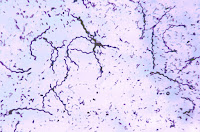

Hona hemen hainbat birusen irudiak. Klikatu irudietan handiago ikusteko..

Batxi 2: Biologia. Bakterio motak

Hona hemen hainbat argazki. Esan ezazu bakoitza zein motatakoa den, itxuraren arabera eta gram tindaketaren arabera.+

Klikatu argazkietan handiago ikusteko.